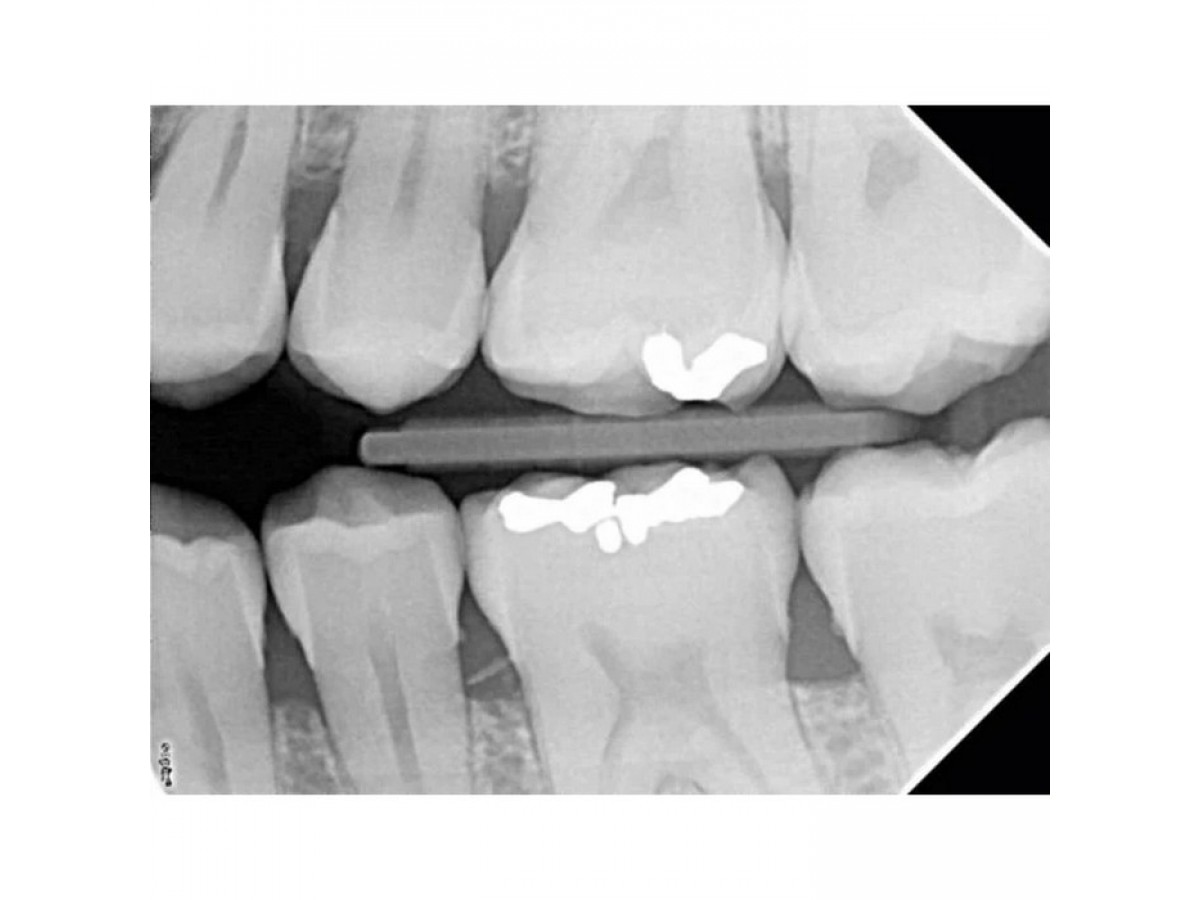

Рентгеновский аппарат X-Mind DC Mobile предназначен для проведения интраоральной дентальной диагностики отдельных зубов, групп зубов, структур челюсти и ротовой полости. Производитель: Satelec Acteon Group .Франция.

С клинической точки зрения эта модель может применяться для ежедневной рутинной диагностики заболеваний зубов и других структур ротовой полости.